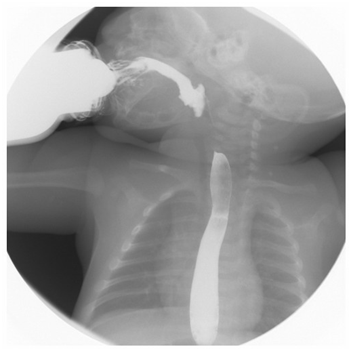

Swallowing study at diagnosis showed a slow oropharyngeal phase, minimum nasopharyngeal reflux, retention of the contrast medium on the floor of the mouth, abnormal anterior/posterior lingual movements, and medium laryngeal penetration (Figure 1). Two spontaneous GER events to the middle third of the esophagus were observed. BAEP reported as normal showing latency of the wave V and of the interval I-V at the upper limits for the left ear.9 several alterations were found throughout the development and neurological examinations during follow up (summarized in Table 1).

Figure 1 Swallowing study at one month of age shows mild pharyngonasal reflux and laryngeal penetration of the barium solution.